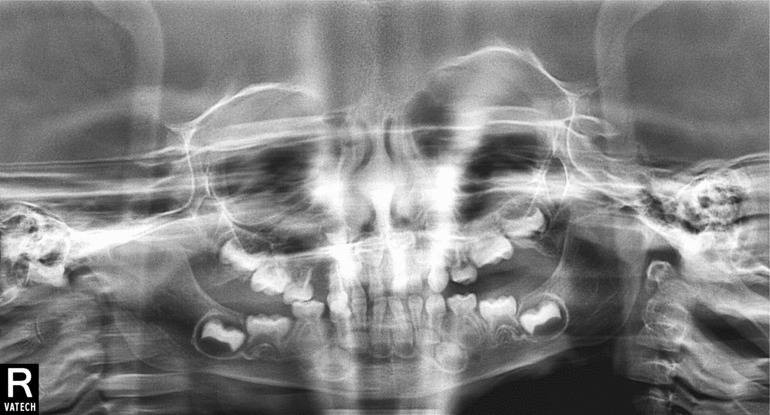

Сходили в субботу на прием в планую клинику, там нам сделали прицельный снимок. Сказали, что это лезет пятерка, а вылезший зуб - это следующий. (у нас такое уже было, что зубки прорезались не по порядку). Сказали, что ничего страшного нет, лечить это не нужно.Но зуб лезет не правильно, под углом, коронкой в щеку. Так же врача смутило, темное пятно между прорезающимся зубом и резцом. Отправила нас на панорамный снимок, после сказала, что они не информативны и нужно еще раз приехать, делать прицельные. на панорамных снимках картина примерно та же, (могу переслать если нужно). Только я белых точечек там не увидела. Только темное пятно.

На приеме говорила что то, что это может быть киста, или какие скопления закладки зубов, я не очень запомнила термины. Очень волнуюсь по этому поводу.